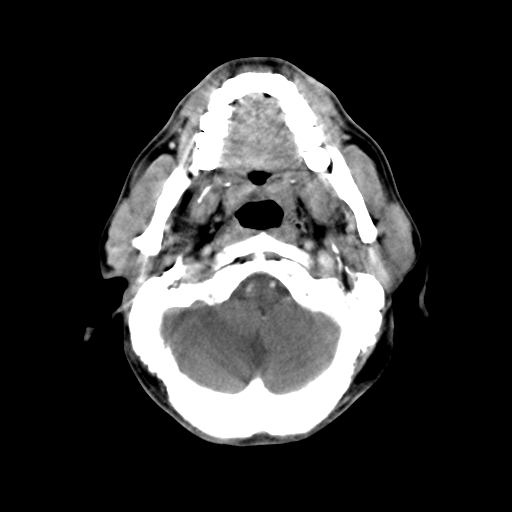

标题: CT24019:男,45岁,发现颈部肿物5个月。 [打印本页]

男,45岁,发现颈部肿物5个月,彩超示:双侧颈部及下颌部软组织增厚。

考虑双侧颈项部良性对称性脂肪增多症。